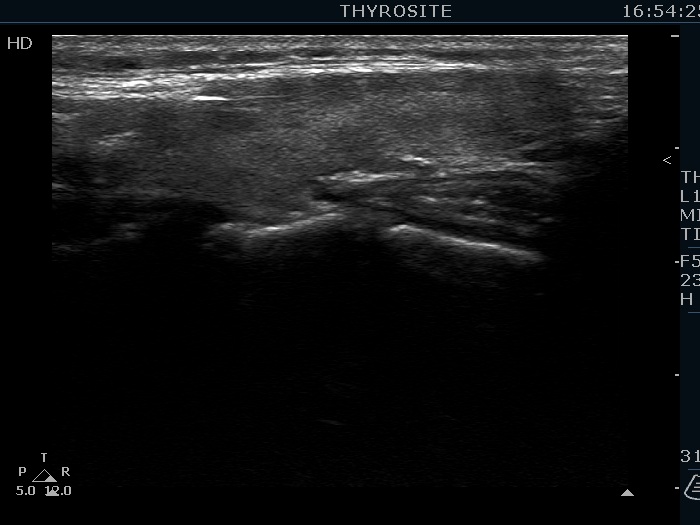

Case 1411 (ultrasonographic picture 5)

Left lobe, longitudinal view.